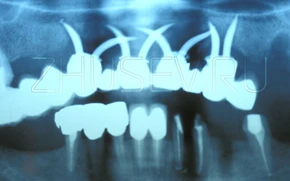

Посмотрите на подборку имплантатов,

они были изготовлены народными умельцами "на коленке" в разные годы.

В этой статье представлены фото имплантатов удаленные мной из пациентов в разные годы. Большинство из них явно сделаны "на коленке в гараже " и пик их производства приходится на начало 90-х годов. Самое удивительное, что фактически, все эти имплантаты исправно выполняли свою функцию в течении нескольких лет, а некоторые "экземпляры" больше 10 лет.

А удалять мне их пришлось из-за того, что у всех этих имплантатов отсутствуют конструкционные и технологические особенности позволяющие служить им гораздо дольше. Большинство из этих пациентов я, после периода заживления (1-4) месяца, переоперировал, установив им более современные конструкции имплантатов. Многие пользуются ими до сих пор. Сейчас все эти имплантаты стали нашей историей. Историей проб и экспериментов.

Пластиночный имплантат. Именно этот тип имплантатов был широко распространен в нашей стране с конца 80-х до середины 90-х годов прошлого века.

Абсолютно кустарный, пластиночный имплантат. На нем даже видны следы механической обработки.

Еще один вариант пластиночного имплантата.